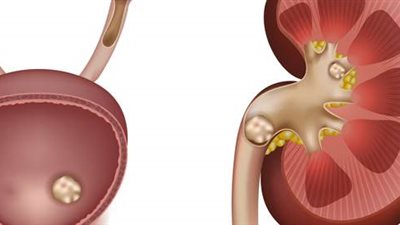

- وأيضًا علاج أمراض الكلى؛ فالكلى تلعب دورًا جوهريًا في التخلص من الفائض، لذا فتشخيص ومعالجة أمراضها يعد خطوة أساسية.

إجراءات الغسيل الكلوي

يعد الغسيل الكلوي بالنسبة للمرضى الذين يعانون من فشل كلوي أو لديهم ارتفاع حاد بالمعدل، إجراءً فعالًا للتخلص من الفائض.